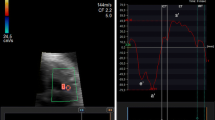

At each examination, a four chamber view of the fetal heart with color overlay in TDI mode was obtained and cine loops of 5-10 consecutive cardiac cycles were recorded. The ultrasound beam was aligned parallel to the interventricular septum with an insonation angle close to zero (<10°). An attempt was made to keep the frame rate >180 frames/s. An off-line analysis was performed using quantitative analysis (Q-analysis) in EchoPAC (GE Vingmed Ultrasound AS, Horten, Norway.) Fixed ROIs of different sizes were placed at the level of the AV-plane in the septum and in the right and left ventricular wall of the fetal heart. ROIs were placed manually at the level of the AV-plane (Fig. 1). The width of the ROI was increased in order to fit the increasing thickness of the septum or the ventricular walls.

The position of region of interest (ROI). The left panel indicates position of the eight different ROI sizes in gestational age group III in the left ventricular wall. Different colors indicate different ROI sizes (height × width). Yellow (2 × 2 mm), turquoise (3 × 3 mm), red (4 × 3 mm), green (4 × 4 mm), orange (6 × 3 mm), pink (6 × 4 mm), grey (8 × 3 mm) and blue (8 × 4 mm). The right panel shows the velocity traces produced. Sm = peak systolic myocardial velocity. Em = peak early diastolic myocardial velocity. Am = peak myocardial velocity during atrial contraction